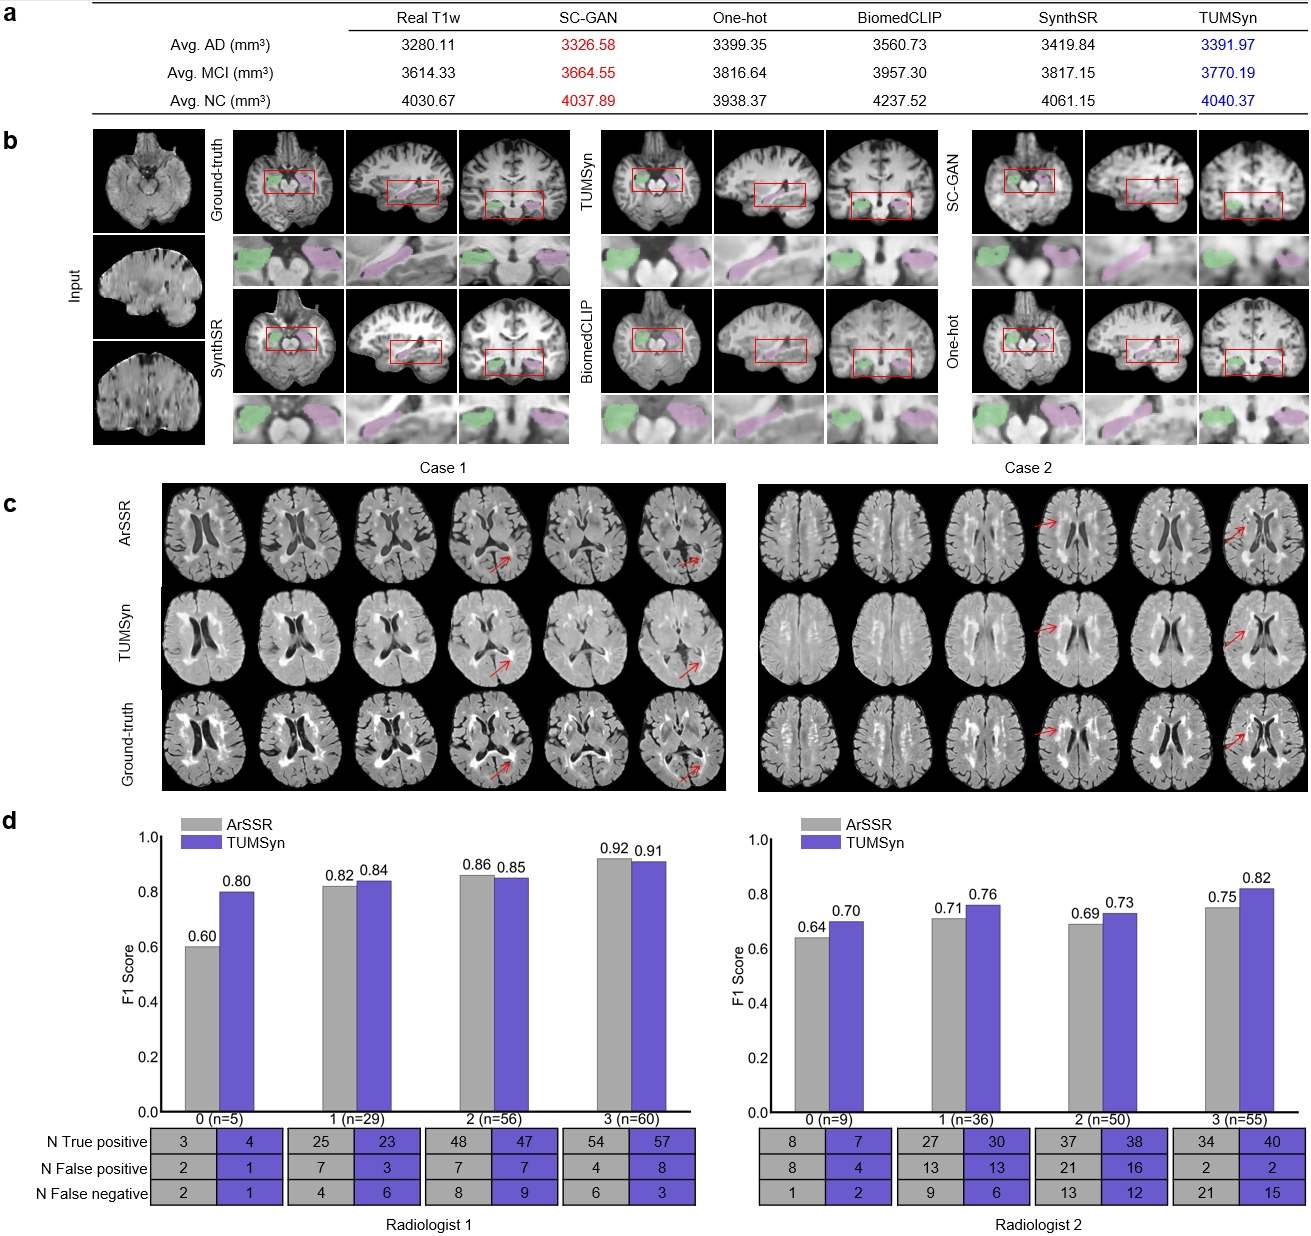

We summarize the average segmented hippocampal volumes of AD, mild cognitive impairment (MCI), and normal controls (NC) subjects by different synthesis methods in Fig.6 a. The results demonstrate high discriminative power among the three disease stages, closely matching the discrimination exhibited by the real T1w scans. Specifically, our approach retains 86% of the average volume difference between AD and NC (648 versus 751 mm3) and 65% between MCI and NC (270 versus 416 mm3). Furthermore, despite our model did not see FLAIR sequences in ADNI during training, compared with SC-GAN, which is trained on this dataset, TUMSyn achieves at most 3% drop in accuracy (i.e., SC-GAN loses 1.4% from 3614.33 mm3 to 3664.56 mm3, while TUMSyn loses 4.3% from 3614.33 mm3 to 3770.19 mm3 in average hippocampal volume of MCI) for the average segmented volumes across different disease stages. This result indicates that despite the large slice spacing of the input FLAIR data and small volume of the hippocampus, TUMSyn recovers most of the missing high-frequency details and anatomical structures compared to other methods in the zero-shot setting, enabling accurate volume estimation. Fig.6 b presents an example of synthesized T1w sequences and segmented hippocampus for an MCI patient using different methods. Visually, the images generated by TUMSyn can most accurately delineate the anatomical structures of various brain regions, providing promising contrast between the hippocampus and surrounding areas. In contrast, other methods, because of lacking super-resolution capabilities and flexible generalizability, produce images that are adversely affected by the low-resolution input, and thus over-smoothed synthesis with diminished structural detail. Both qualitative and quantitative observations are inline with the evaluation in Table 2.

Application in grading of cerebral small vessel disease

To validate the potential clinical utility of TUMSyn in identifying white matter hyperintensities (WMH), a type of focal lesion frequently observed in cerebral small vessel diseases (CSVD) and the aging population, we undertake an assessment using 150 subjects in the external dataset from Ren Ji Hospital. Two proficient radiologists conducted Fazekas scale [31] grading on (1) real-acquired FLAIR sequences, (2) synthesized FLAIR sequences generated by TUMSyn, and (3) synthesized FLAIR sequences generated by ArSSR (trained on this dataset). The Fazekas scale ranging from 0 to 3 categorizes the severity of the WMH lesion burden from absence to high burden of WMH lesions, respectively.

Fig.6 c represents two cases of the axial plane of ground-truth and synthesized FLAIR images by TUMSyn and ArSSR. Surprisingly, in a zero-shot setting, TUMSyn achieves superior lesion synthesis, demonstrating improved lesion morphologies and contrast in both subcortical (Case 1) and cortical (Case 2) regions compared to trained ArSSR. According to visual assessments of image quality, radiologists can visually differentiate between real and virtual FLAIR images in most cases. Their discrimination is primarily based in the intensity and texture, rather than the appearance of the lesion regions. To quantitatively evaluate the performance of both methods, we show the F1 scores of the Fazekas scale across four grades between the real FLAIR and the synthesized ones in Fig.6 d. The results indicate that the performance of our method surpasses ARSSR in most of cases. Specifically, this superiority is observed in radiologist 1’s evaluation for Fazekas grades 0 and 1, and in radiologist 2’s evaluation for Fazekas grades 0, 1, 2 and 3. We hypothesize that this superior performance may be attributed to the universal learning on large-scale datasets encompassing a diverse range of brain images with abnormalities, including the presence or absence of such WMH patterns.